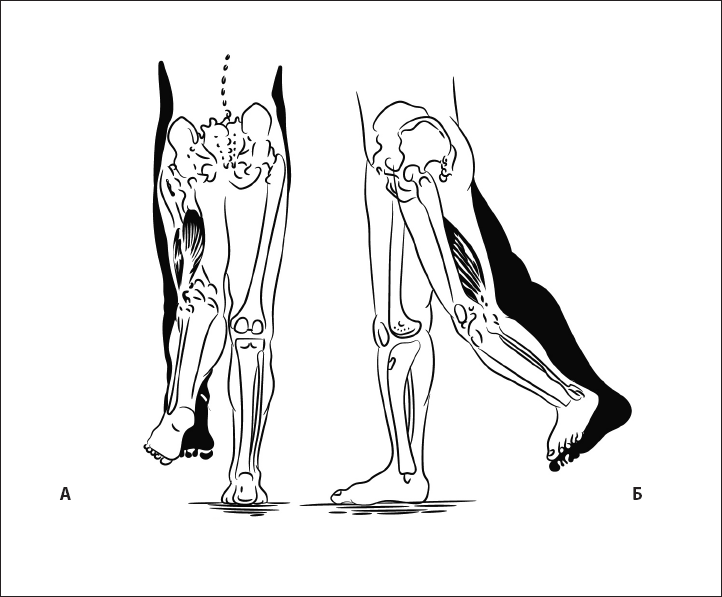

Рис. 36. Экстензия бедра с наружной ротацией стопы при укорочении двуглавой мышцы бедра. А – вид сзади. Б – вид сбоку.

Рис. 37. Экстензия бедра с внутренней ротацией стопы при укорочении полусухожильной и полумембранозной мышц. А – вид сзади, Б – вид сбоку.